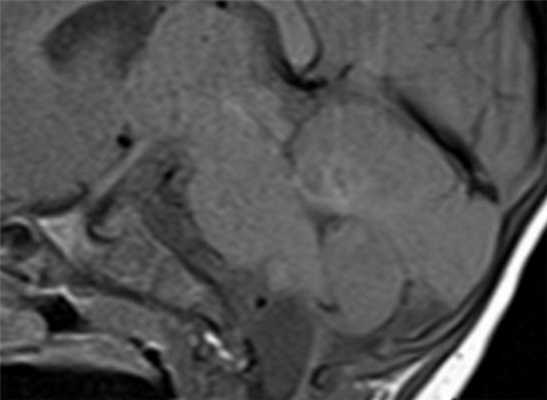

МРТ головного мозга. Арахноидальная киста полюса левой височной доли. Цветовая обработка.

Кисты головного мозга - это аномалии его развития. При МРТ в СПб мы видим задачу в дифференциальной диагностике с кистозными формами опухолей. При МРТ головного мозга некоторые виды кист, особенно дермоидные, сами напоминают опухоль.

Арахноидальные кисты представляют собой скопление ликвора между листками расщепленной паутинной оболочки. Арахноидальная киста обычно не сопровождается другими мальформациями. Незначительная часть арахноидальных кист имеет приобретенное происхождение - следствие лептоменингита, операции или кровоизлияния. Частота составляет около 1% от внутричерепных образований. Соотношение полов М:Ж, как 4:1. Типичная локализация - средняя черепная ямка (в области Сильвиевой борозды 50%), межполушарная щель, мосто-мозжечковый угол (11%), за скатом или на уровне четверохолмия (10%), в области червя мозжечка (9%), реже в области межножковой и предмостовой цистерн (3%), а также супраселлярной и хиазмальной цистерн. В зависимости от размера предложено делить кисты на 3 типа (Galassi, 2006), что однако, не имеет практического значения. Ретроцеребеллярная арахноидальная киста довольно часто встречаются за мозжечком и отличима от mega cisterna только по неизменённой задней черепной ямке. При МРТ головного мозга содержимое кисты чисто ликворное, стенки гладкие, чётко очерченные, внутри кисты могут быть перегородки. Мелкие арахноидальные кисты очень трудно увидеть при МРТ головного мозга. Меняя ширину окна и его уровень на Т1-зависимых МРТ изображениях можно заметить, что киста чуть светлее ликвора. Дифференциальная диагностика с эпидермальными кистами лучше осуществляется с помощью МРТ последовательности FLAIR. На них при МРТ головного мозга эпидермальные кисты становятся яркими, в отличие от гипоинтенсивных арахноидальных. Вероятно, вариантом арахноидальной кисты является нейроэпителиальная киста, которая при МРТ головного мозга имеет типичное расположение в области хориоидальной щели.